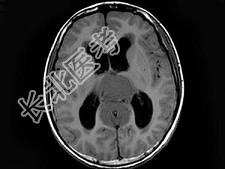

- 单项选择题男,16岁, 头痛数月,MRI平扫及增强扫描如图, 最可能的诊断是 ( )

A、生殖细胞瘤

B、松果体细胞瘤

C、星形细胞瘤

D、室管膜瘤

E、未见异常